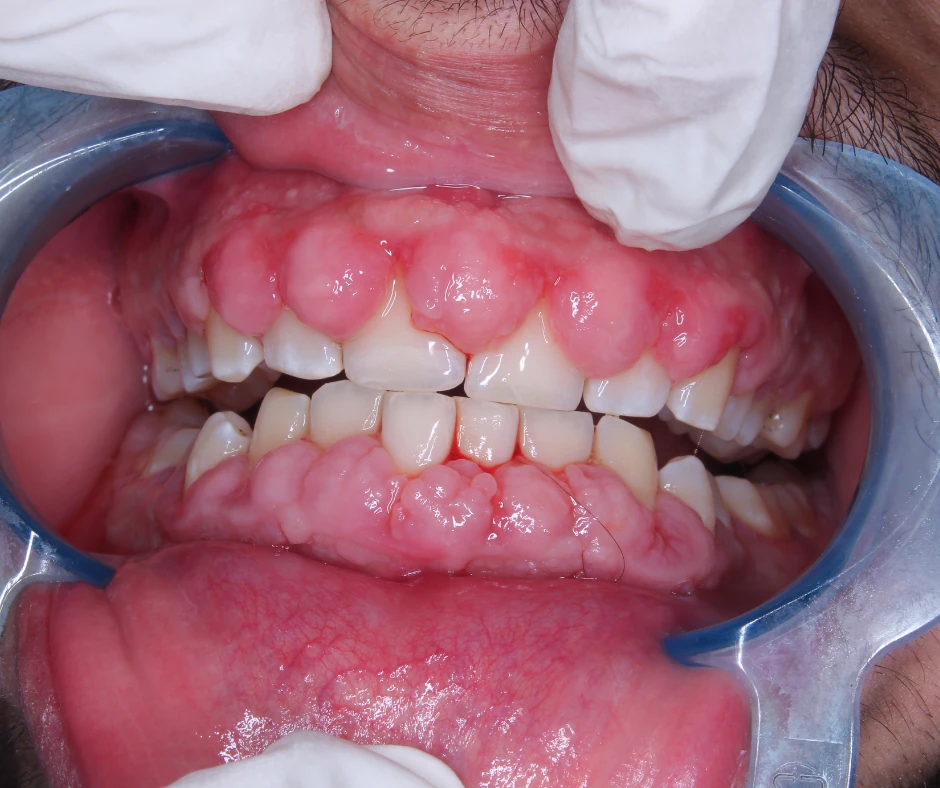

Recognizing gingival hyperplasia early allows for prompt intervention and better outcomes. The condition typically begins with subtle thickening of the gum tissue, particularly in the areas between teeth called the interdental papillae. As the enlargement progresses, the gingiva becomes increasingly swollen, firm, and may develop a nodular appearance with a stippled or smooth surface texture.

Patients with gingival overgrowth often notice that their gums appear larger than normal, sometimes covering portions of the tooth crowns. The enlarged gum tissue may feel firm rather than soft, distinguishing gingival hyperplasia from simple inflammatory swelling. Bleeding, especially during brushing or flossing, is common with this condition, as the deep pockets created by overgrown tissue harbor bacteria that cause gingival inflammation. Some patients experience discomfort or sensitivity around the affected areas, though gingival enlargement itself is not typically painful unless infection develops.

Clinical examination focuses on distinguishing gingival hyperplasia from other conditions that cause gum enlargement. Inflammatory gingival enlargement due to gingivitis or periodontal disease appears red, soft, and bleeds easily, whereas drug-induced or hereditary gingival fibromatosis typically presents with firmer, more fibrous tissue that may be pink or pale. The distribution pattern also provides diagnostic clues—drug-induced gingival enlargement often affects the front teeth most prominently, while hereditary fibromatosis tends to involve the entire gingiva uniformly.